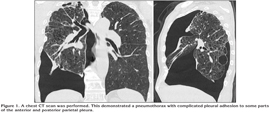

A 77-year-old man presented with acute breathlessness. He had a history of smoking 20 cigarettes per day for 45 years, but stopped smoking at the age of 74. He had pneumothorax of the right three times, which was treated surgically two times. On arrival, he was clear and ambulatory. The vital signs were stable: blood pressure was 130/80 mmHg, pulse rate 84 beats per minute, respiratory rate 16 breaths per minute, and body temperature 37.0?C. Physically, auscultation of the lung revealed clear breath sounds except over the left lung field where breath sounds were diminished. The remainder of the physical examination was unremarkable. A plain chest radiograph demonstrated a right pneumothorax with complicated pleural adhesion. Arterial blood gas analysis revealed that PaO2 was 64.2 torr, PaCO2 43.2 torr, and pH 7.418. As the postero-anterior radiograph demonstrated a pneumothorax with pleural adhesion, therefore, a chest CT scan was performed. This demonstrated a pneumothorax with complicated pleural adhesion to some parts of the anterior and posterior parietal pleura (Figure 1). A drainage tube (Aspiration Kit: 6 Fr) was inserted avoiding the pleural adhesion parts not to injure the lung. The complicated pneumothorax was successfully treated with the chest tube.

In our patient, management of the postoperative complicated pneumothorax was greatly enhanced by a CT scan. The CT scan confirmed the diagnosis, demonstrated the site and size of the pneumothorax, identified complicated adhesions between visceral pleura and chest wall, and indicated the optimum site of drainage. The plain chest radiograph did not prove to be sufficient for therapeutic decision-making. Therefore, in patients who develop postoperative recurrent pneumothorax, it is mandatory to perform chest CT scan and evaluate the presence of complicated pleural adhesions. To find the optimal insertion part for chest drainage tube, chest CT scan can provide useful information. The degree of complicated pneumothorax seen on the chest CT scan may be difficult to find the optimum site of drainage.